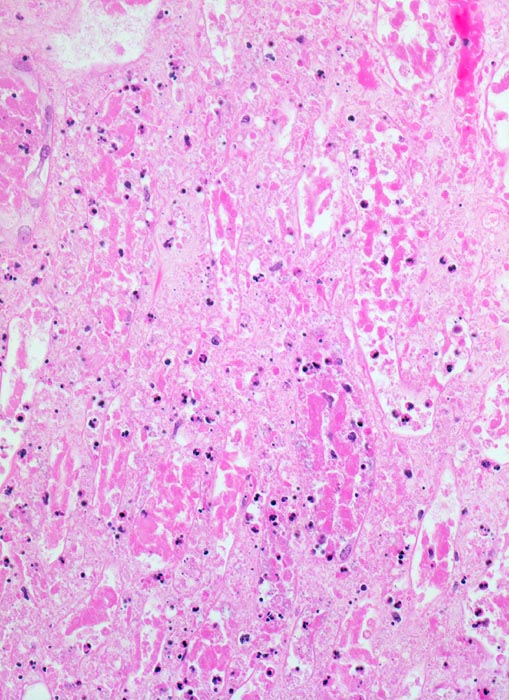

akuter Niereninfarkt: Koagulationsnekrose

Vollständig nekrotische Tubuli ohne erkennbare Zellkerne. Die Nekrose ist durchsetzt von zerfallenden neutrophilen Granulozyten. Die schwarzen Punkte entsprechen Kerntrümmern der Granulozyten.

Chronisches Vorhofflimmern mit Morbus embolicus: anämische Infarkte verschiedenen Alters in beiden Nieren und in der Milz. Alte abgebaute Enzephalomalazie im Versorgungsbereich der Arteria cerebri media rechts.